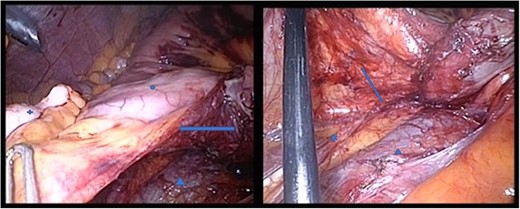

A 37-year-old patient presented with acute abdominal pain which was colicky in nature and accompanied by nausea and repeated vomiting. Physical examination showed tenderness in the right lower abdomen and guarding in all four quadrants. There was no history of previous abdominal surgery. A computed tomography (CT) scan revealed the mechanical obstruction of the small bowel and the suspicion of a pre-existing paraduodenal hernia in the right upper abdomen (Figs 1 and 2). Fortunately, the patient’s condition improved significantly following the administration of analgesia, and the initial conservative treatment was continued. An X-ray with oral contrast agent enhanced the suspicion of a right-sided paraduodenal hernia. As the patient was now pain free, we scheduled an elective diagnostic laparoscopy 3 weeks later.

Between the head of pancreas and the lower edge of the liver, an oval-shaped, clearly defined convolution of small intestine loops measuring ~9.5 x 6.5 cm was visible. The duodenum could not be followed as expected—there is no duodenal part crossing the vessels to the left

In the coronal plane, in addition to the suspicion of an internal hernia, a short intussusception was also suspected. Furthermore, this level shows that the herniating small intestine is located on the right, while the left side of abdomen appears empty